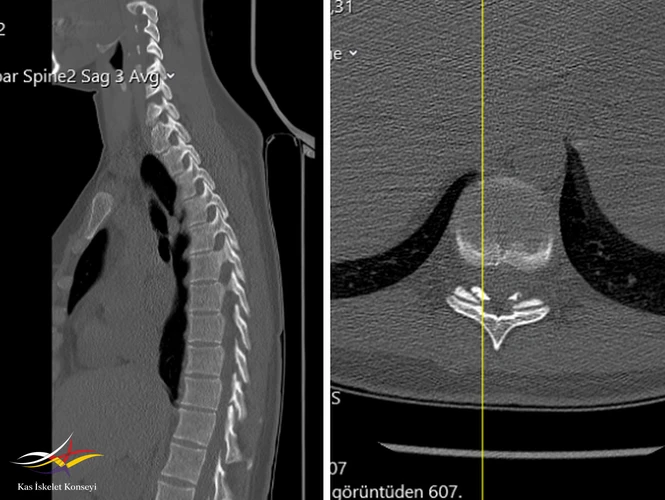

Resim 2. BT incelemesi aynı seviyede ligamentum flavum kalsifikasyonu gösteriyor.

Sırt ağrısını açıklayacak başka bir neden bulunamaması nedeniyle, tek seviyede saptanan bu alt torasik dejenere disk seviyesinin semptomların kaynağı olduğu düşünüldü. BT'de bu seviyede saptanan ligamentum flavum kalınlaşmasının bu seviyedeki mekanik yüklenme ve anormal biyomekaniğin bulgusu olduğu düşünüldü. Tanı tedavi amaçlı faset + epidural enjeksiyon planlanabileceği; egzersizin ve korse kullanımının uygun olduğu; ağrının tüm bu konservatif tedavilere yanıt vermemesi ve günlük hayatı etkileyecek seviyede olması durumunda son seçenek olarak basit diskektomiden ziyade bir stabilizasyon operasyonuna gidilebileceği tartışıldı.